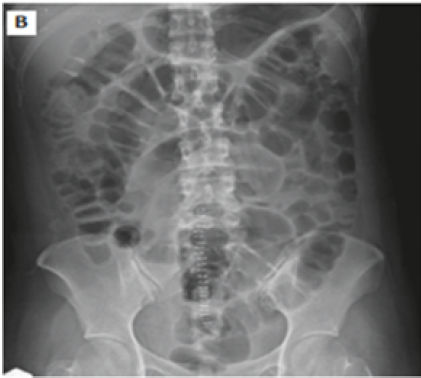

Figure 2: Abdominal X-ray Showing Ileus